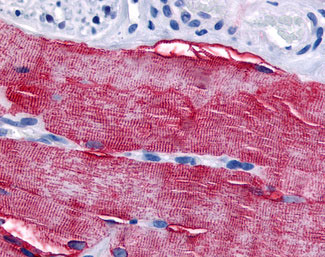

Anti-GRK5 antibody APR02012G IHC of human skeletal muscle. |